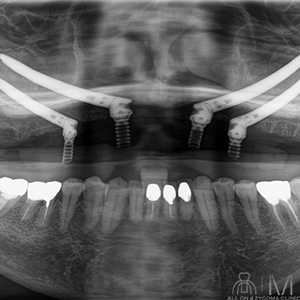

術後パノラマ画像所見

上顎に4本ザイゴマインプラントと4本のアバットメントにテンポラリーシリンダーが装着されているのを認める。左右の上顎洞に明らかな曇りは認めない。